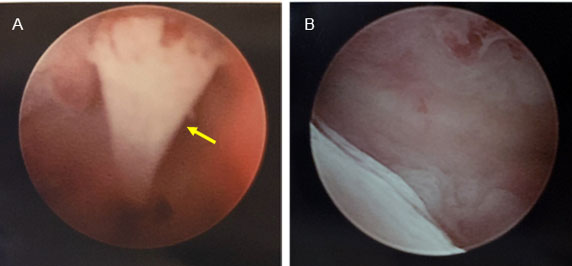

Figure 3: Before and after images during bone retrieval through hysteroscopy. The first image identifies the fetal bone and the second image shows complete removal of all bone from the uterine cavity. (A) Hysteroscopic images showing presence of an identifiable fetal femur bone from the uterine canal. (B) No further bony fragments are visualized after complete removal.

The echogenic substance was removed via operative hysteroscopy by transabdominal ultrasound guidance two months after its identification on ultrasound. The size, shape, color, consistency, and overall appearance of the foreign body was consistent with fetal bone. The foreign body was approximately 22 mm in length, which correlates with an estimated gestational age of 15 weeks and the timing of the patient’s most recent abortion. It was determined clinically that the echogenic substance was fetal bone (Figure 3). The bone was positioned linearly between the fundus and the anterior aspect of the lower uterine segment. The bone was grasped at the distal end and removed intact. The fundal aspect of the bone left a small indentation in the endometrium without extension into the myometrium. This was the only bony piece identified and removed. Complete removal was confirmed with ultrasound and hysteroscopy.